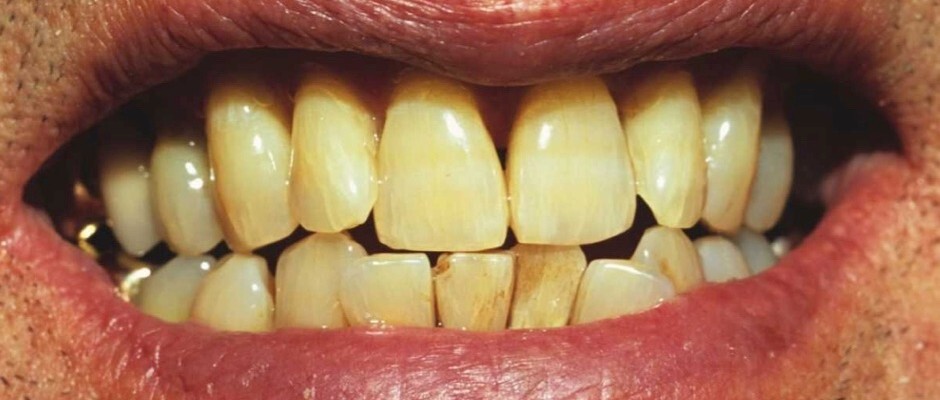

If you’re not the type of person who takes a lot of time in your appearance, or even thinks of this as shallow, you might be wondering if yellowing teeth is a sign of any health concerns, or if it’s simply an aesthetic issue. This depends on the source of the yellowing. Yellowing can be linked to a few different sources, and for the most part, they’re harmless. Here are some reasons your teeth might be yellowing over time.

Aging

One of the downsides to getting older is that your teeth naturally begin to turn more yellow. As part of the aging process, enamel on our teeth naturally wears thin. Dentin, which is the inner layer of your teeth, has a naturally darker appearance and starts showing through your enamel, or the thin, top layer of your teeth. There are ways you can slow enamel thinning, such as avoiding overly sugary or acidic foods and keeping acid reflux under control. However,  it’s natural for some darkening to occur, often giving the appearance of yellow teeth.

Genetics

You might not have known this but teeth yellowing can actually be due to your DNA. In the same way that your parents and ancestry influences your hair, skin and eye color, they can influence the color of your teeth. This is because of the thinness of your enamel. If you naturally have thinner enamel, your darker dentin will start to show, just as we mentioned in the last section.

Chemicals

There are some childhood medications that can affect the yellowing of teeth. This is because some ingested chemicals in those medications can damage your dentin. Tetracycline, an antibiotic that is sometimes used to also treat asthma and allergies can yellow or otherwise discolor teeth. Now that we know this, many doctors know that it’s best to hold off on prescribing these until about age 10, but if you took this or a drug that reacts in a similar way, you might be left with those lasting effects. Chemotherapy and other radiations can also affect this.

Yellowing teeth can be caused by medical reasons, but none of them are especially concerning. However, yellow teeth aren’t very aesthetically pleasing in the eyes of most. As mentioned before, taking care of your teeth is a great way to build self confidence, so even if you’re someone who doesn’t spend much time worrying about your appearance, having your teeth whitenedonce a year can go a long way in building your self esteem.